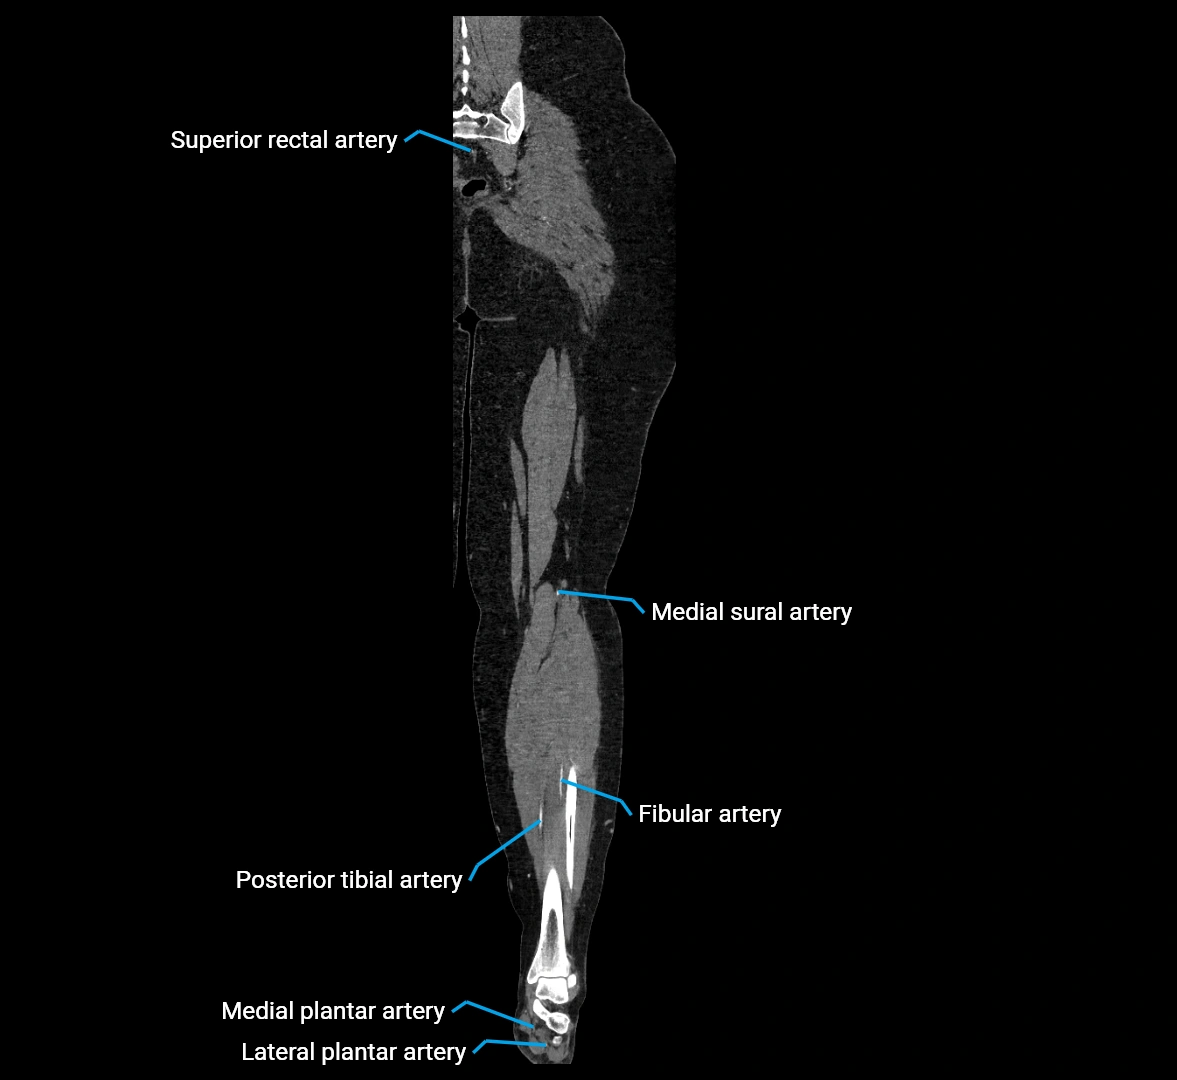

MRI images

image